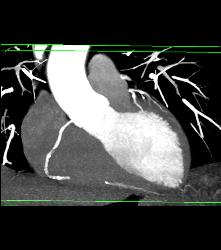

Left Anterior Descending Coronary Artery (LAD) and Right Coronary Artery (RCA) Disease